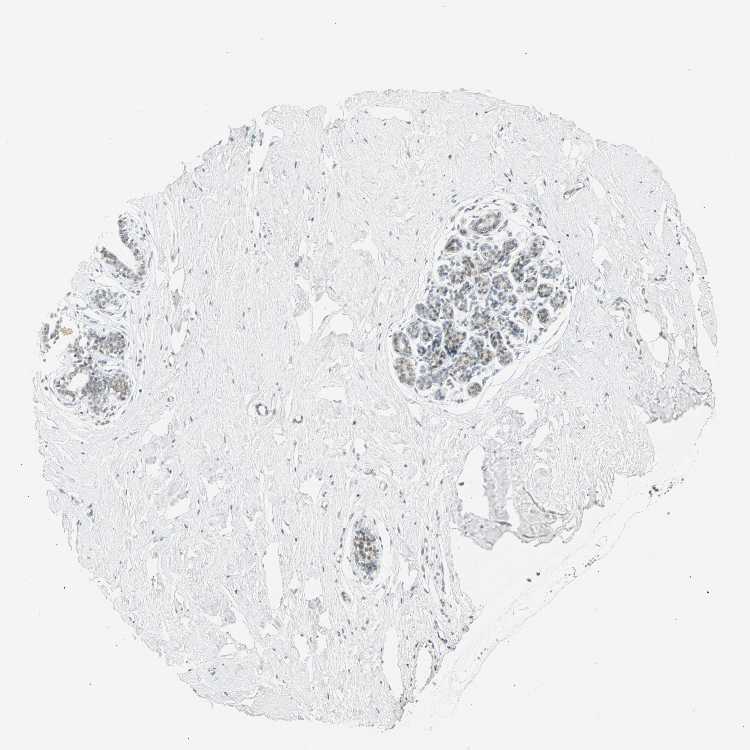

BREAST - Antibody stainingi

Antibody staining in the annotated cell types in the current human tissue is reported as not detected, low, medium, or high, based on conventional immunohistochemistry profiling in selected tissues. This score is based on the combination of the staining intensity and fraction of stained cells.

Each image is clickable and will lead to virtual microscopy that enables deeper exploration of all samples and also displays staining intensity scores, fraction scores and subcellular localization as well as patient and tissue information for each sample.

Antibody HPA067203Antibody CAB008094

Adipocytes Not detectedMedium

Glandular cells Not detectedMedium

Myoepithelial cells Not detectedNot detected